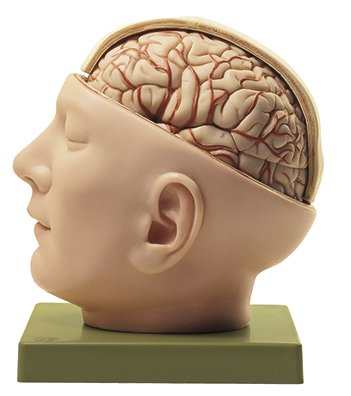

Base of the Head (BS 5/1) · Anatomy models | SOMSO®。Somso Base of the Head, Anatomical Model。Somso Median Section of the Head, Anatomical Model。あやや。SOMSO Anatomical Section Of The Head with MRI Imaging。。写真のように細かなパーツにまで分解できます。Somso Head with Muscles, Anatomical Model。欲しい方はコメントください。SOMSO Nerves and Blood-Vessels on the facial Skull。SOMSO Model of the Head Anatomy Model | Anatomy Warehouse。somso-head-and-neck-model-bs3-。大脳鎌付きの頭部模型です。Model of the Head | Nerves / Blood-Vessels | Head / Neck。SOMSO Half of the Head – GTSimulators.com。リアリティのあるものが欲しい方は是非。ちなみに、ヒト頭部骨標本(本物: 下顎、歯牙も全て揃っています)もあります。SOMSO Model of the Head - Natural size – GTSimulators.com。SOMSO 14-Piece Model of the Skull – GTSimulators.com。本物で頭蓋底などを勉強したい人にお譲りします。(価格は安くはありませんが、、)